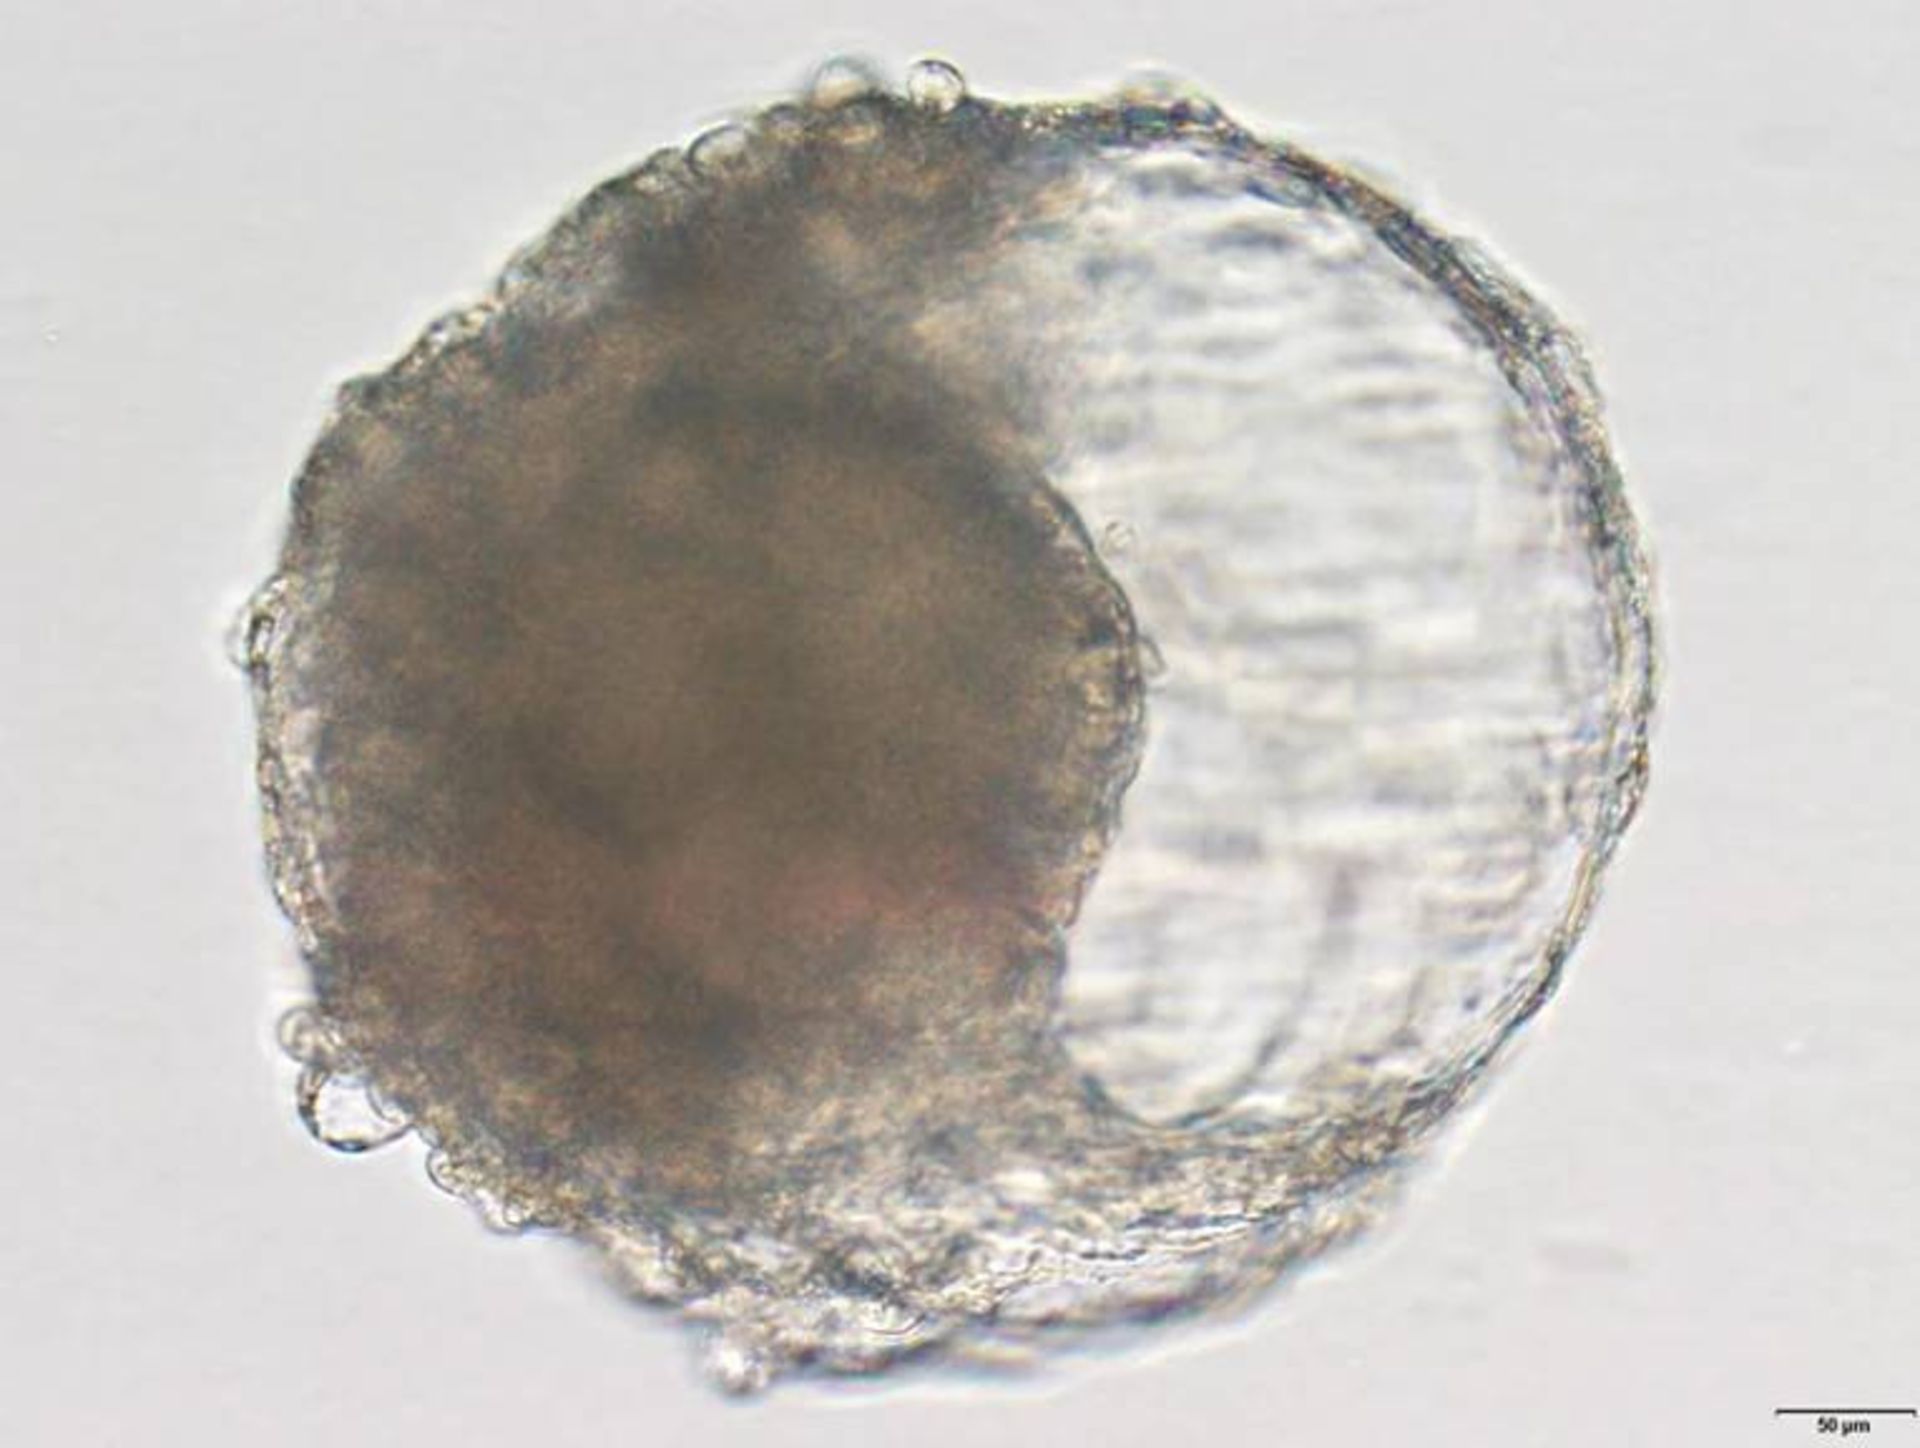

مدل رویان بلاستوئید

بلاستوئید

بلاستوئید ایجادشده از سلول‌های بنیادی میمون ﺳـﯿﻨﻮﻣﻮﻟﮕﻮس. این بلاستوئید شبیه مراحل ابتدایی رویان است و وقتی در رحم میمون کاشته شد، موجب تغییراتی شبیه بارداری شد.